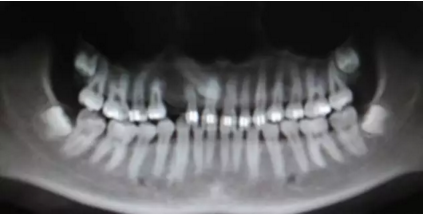

阻生齒外科聯(lián)合正畸治療

26.png

27.png